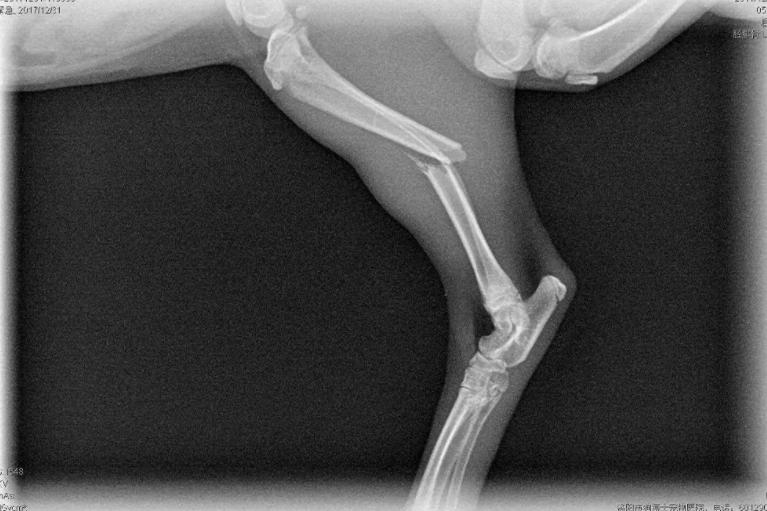

(一)

四肢骨折是猫咪最常见的骨折。

绝大部分由外伤导致,

也是冬季在家最容易出现的猫咪伤病之一,

无论是从高处跌落,

还是被门挤到爪子,

甚或是猫猫之间打架斗殴都可能会把骨头折断。

一些幼龄猫或体态过于肥胖的猫的骨质更脆弱,

或承受的压力更大,也更容易出现四肢骨折。

轻微的骨折通过观察和触诊很难确诊,

建议铲屎官带猫咪进行X光片检查。